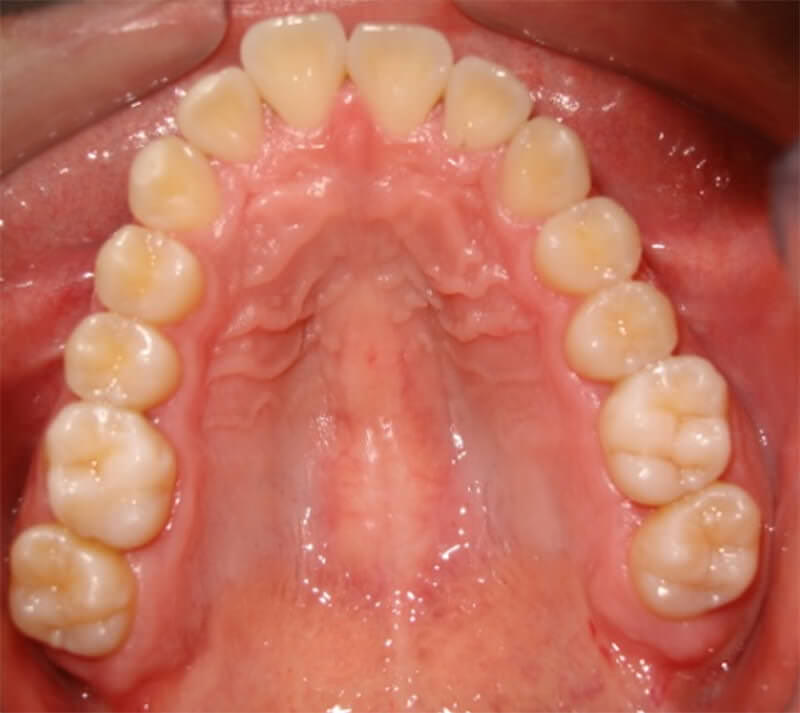

El presente caso se trata de un paciente masculino de 22 años de edad, natural y procedente de Caracas, que acude a consulta referido para evaluación y tratamiento terceros molares. Al examen clínico extrabucal (Figura Nº 1), se presenta sin lesión aparente. Al examen clínico intrabucal, presenta aumento de volumen en zona distal del segundo molar superior derecho (Figura Nº2). Al examen radiográfico, se presenta una imagen radiopaca compatible con estructura dentaria del tercer molar superior derecho, asociado a una imagen radiopaca de bordes definidos de 3 cm de diámetro en cercanía con la cortical del piso del seno maxilar (Figura Nº3). Se realizó tomografía computarizada con cortes axiales, coronales y sagitales, donde se observo una imagen hiperdensa asociada al tercer molar superior derecho, en íntima relación con la cortical del piso del seno maxilar (Figura Nº4). Se procede a realizar biopsia excisional de la lesión y odontectomia de los terceros molares, presentándose como complicación peri-operatoria una comunicación bucosinusal, donde se realiza cierre con colgajo de avance recto (Figura Nº 5, 6, 7). Se realiza un control post-operatorio a los 7 días para retiro de sutura, observándose evolución satisfactoria. Posteriormente, a los 6 meses se realiza un segundo control evidenciándose correcta cicatrización de los tejidos blandos y duros (Figura Nº 8 y 9)

Figura Nº8. Control post-operatoria 6 meses. Vista oclusal

Cortesía del Ambulatorio Parque deportivo Miranda – Corposalud Miranda

Figura Nº9. Control post-operatoria 6 meses. Vista oclusal